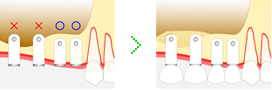

サイナスリフト法

サイナスリフトはソケットリフトと同じく、上顎の骨造成を合わせたインプラント治療法ですが、違いはサイナスリフトの場合は歯槽骨が3mm以下の場合に行います。

サイナスリフトはソケットリフトと同じく、上顎の骨造成を合わせたインプラント治療法ですが、違いはサイナスリフトの場合は歯槽骨が3mm以下の場合に行います。

歯ぐきの側面から切開し、骨の移植を行います。

ソケットリフトのように、上顎洞に骨を押し上げるのではなく、上顎洞の外にあるシュナイダー膜を歯槽骨から剥がすことでスペースをつくります。